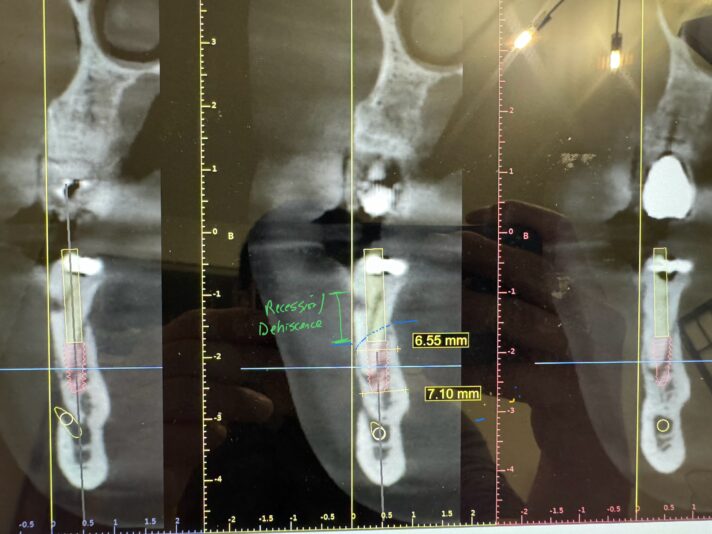

#20 is planned for an extraction. Patient wants to know fixed options so my thought is bridge #20-x-x-18 (not the greatest option due to bone loss on both abutment teeth) or implant #20 and #19. The ridge width around #20 is naturally narrow (6.5-7mm – virtual implant I placed Is 3.5×8.5mm). #20 also has 4mm buccal recession/dehiscence…